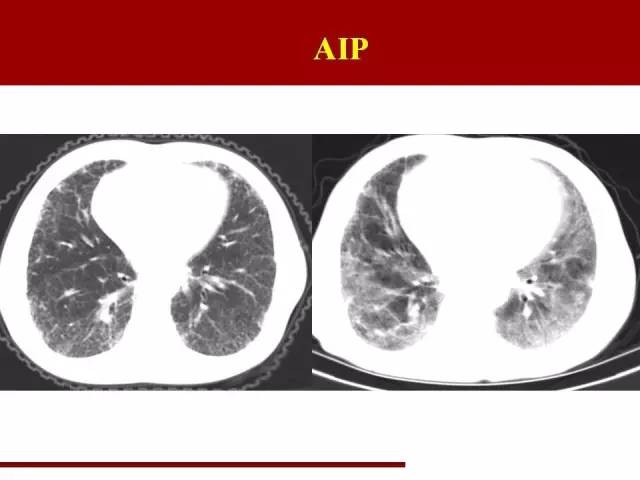

AIP一个特点:快

进展迅速是其特点

在原有的间质性肺炎的基础上迅速进展

这个诊断没有十足把握建议不要轻易下

因为下完之后就几乎判死刑,大部分病人在一个月内死亡